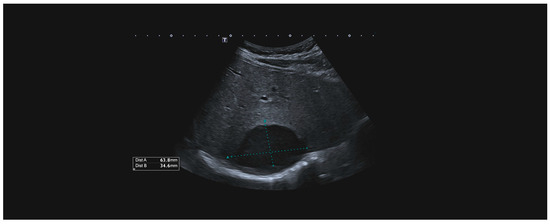

Rare Complication of Cardiopulmonary Resuscitation—Liver Injury

by David Hoskovec, Pavol Klobušický, Adam Pudlač, Matyáš Lochman, Zdeněk Krška and Petr Dytrych

Medicina 2024, 60(9), 1470; https://doi.org/10.3390/medicina60091470 - 9 Sep 2024

Background and Objectives: Liver injury is a rare complication of cardiopulmonary resuscitation. Correct and early diagnosis and treatment are essential. The clinical signs of injury may be masked by the cardiac arrest. We present a single-centre retrospective observational study of traumatic liver [...] Read more.

Background and Objectives: Liver injury is a rare complication of cardiopulmonary resuscitation. Correct and early diagnosis and treatment are essential. The clinical signs of injury may be masked by the cardiac arrest. We present a single-centre retrospective observational study of traumatic liver injury after cardiopulmonary resuscitation. Materials and Methods: A retrospective analysis of the patients treated for liver injury after cardiopulmonary resuscitation was conducted. Demographic data, the cause of resuscitation, the duration of restoration of spontaneous circulation (ROSC), and the surgical approach were analysed. Results: We have treated nine patients with severe liver injury after cardiopulmonary resuscitation. The diagnosis was made on the basis of cardiopulmonary instability, a fall in the erythrocyte count in eight cases, and was confirmed by CT or ultrasound examination. The last one was diagnosed accidentally on MR. Surgery, in cases of unstable patients, was followed immediately after a diagnosis. We combined liver sutures and intra-abdominal packing with a planned second-look surgery. Five of the nine patients survived. Conclusions: Liver injury after cardiopulmonary resuscitation is rare and is associated with high mortality. The recurrence of cardiopulmonary instability and/or a low or falling red blood cell count are the main signs of this injury. Bedside ultrasound and CT scans are the most important methods to confirm the diagnosis. The rule of surgical repair is the same as in all liver injuries, regardless of aetiology. The key factors for survival include early diagnosis, together with the length of restoration of spontaneous circulation (ROSC). Full article

Show Figures

Figure 1